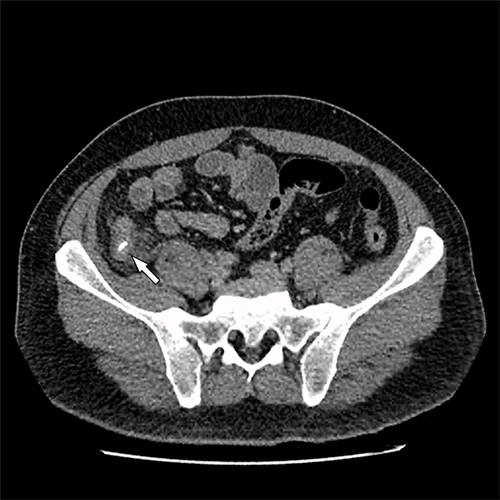

A 41-year-old, previously well, male presented to the emergency department with lower abdominal pain, pyrexia with a temperature of 38.2°C and a palpable suprapubic mass. His relevant background history included an uneventful laparoscopic appendicectomy 2 years prior for acute appendicitis, insulin independent type 2 diabetes and hypertension. He presented with raised inflammatory markers and computed tomography (CT) showing a well circumscribed central pelvis lesion that appeared concerning for a urachal malignancy (Fig. 1). This lesion was closely associated with the dome of the bladder (Fig. 2). This supracystic lesion measured 58 mm × 56 mm with central cystic component of 15 mm in diameter, and contained a 11 mm central calcification. Further characterization with magnetic resonance imaging showed possible extension of this mass to the rectus abdominis without significant lymphadenopathy (Fig. 3). Flexible cystoscopy only found inflammation at the dome. As urachal malignancy could not be unequivocally excluded on imaging studies alone, following multidisciplinary discussion, the decision was made to perform an excision of this lesion.

Axial CT image of the pelvic lesion. Arrow indicates central calcification. Arrowhead indicates involvement of anterior abdominal wall.